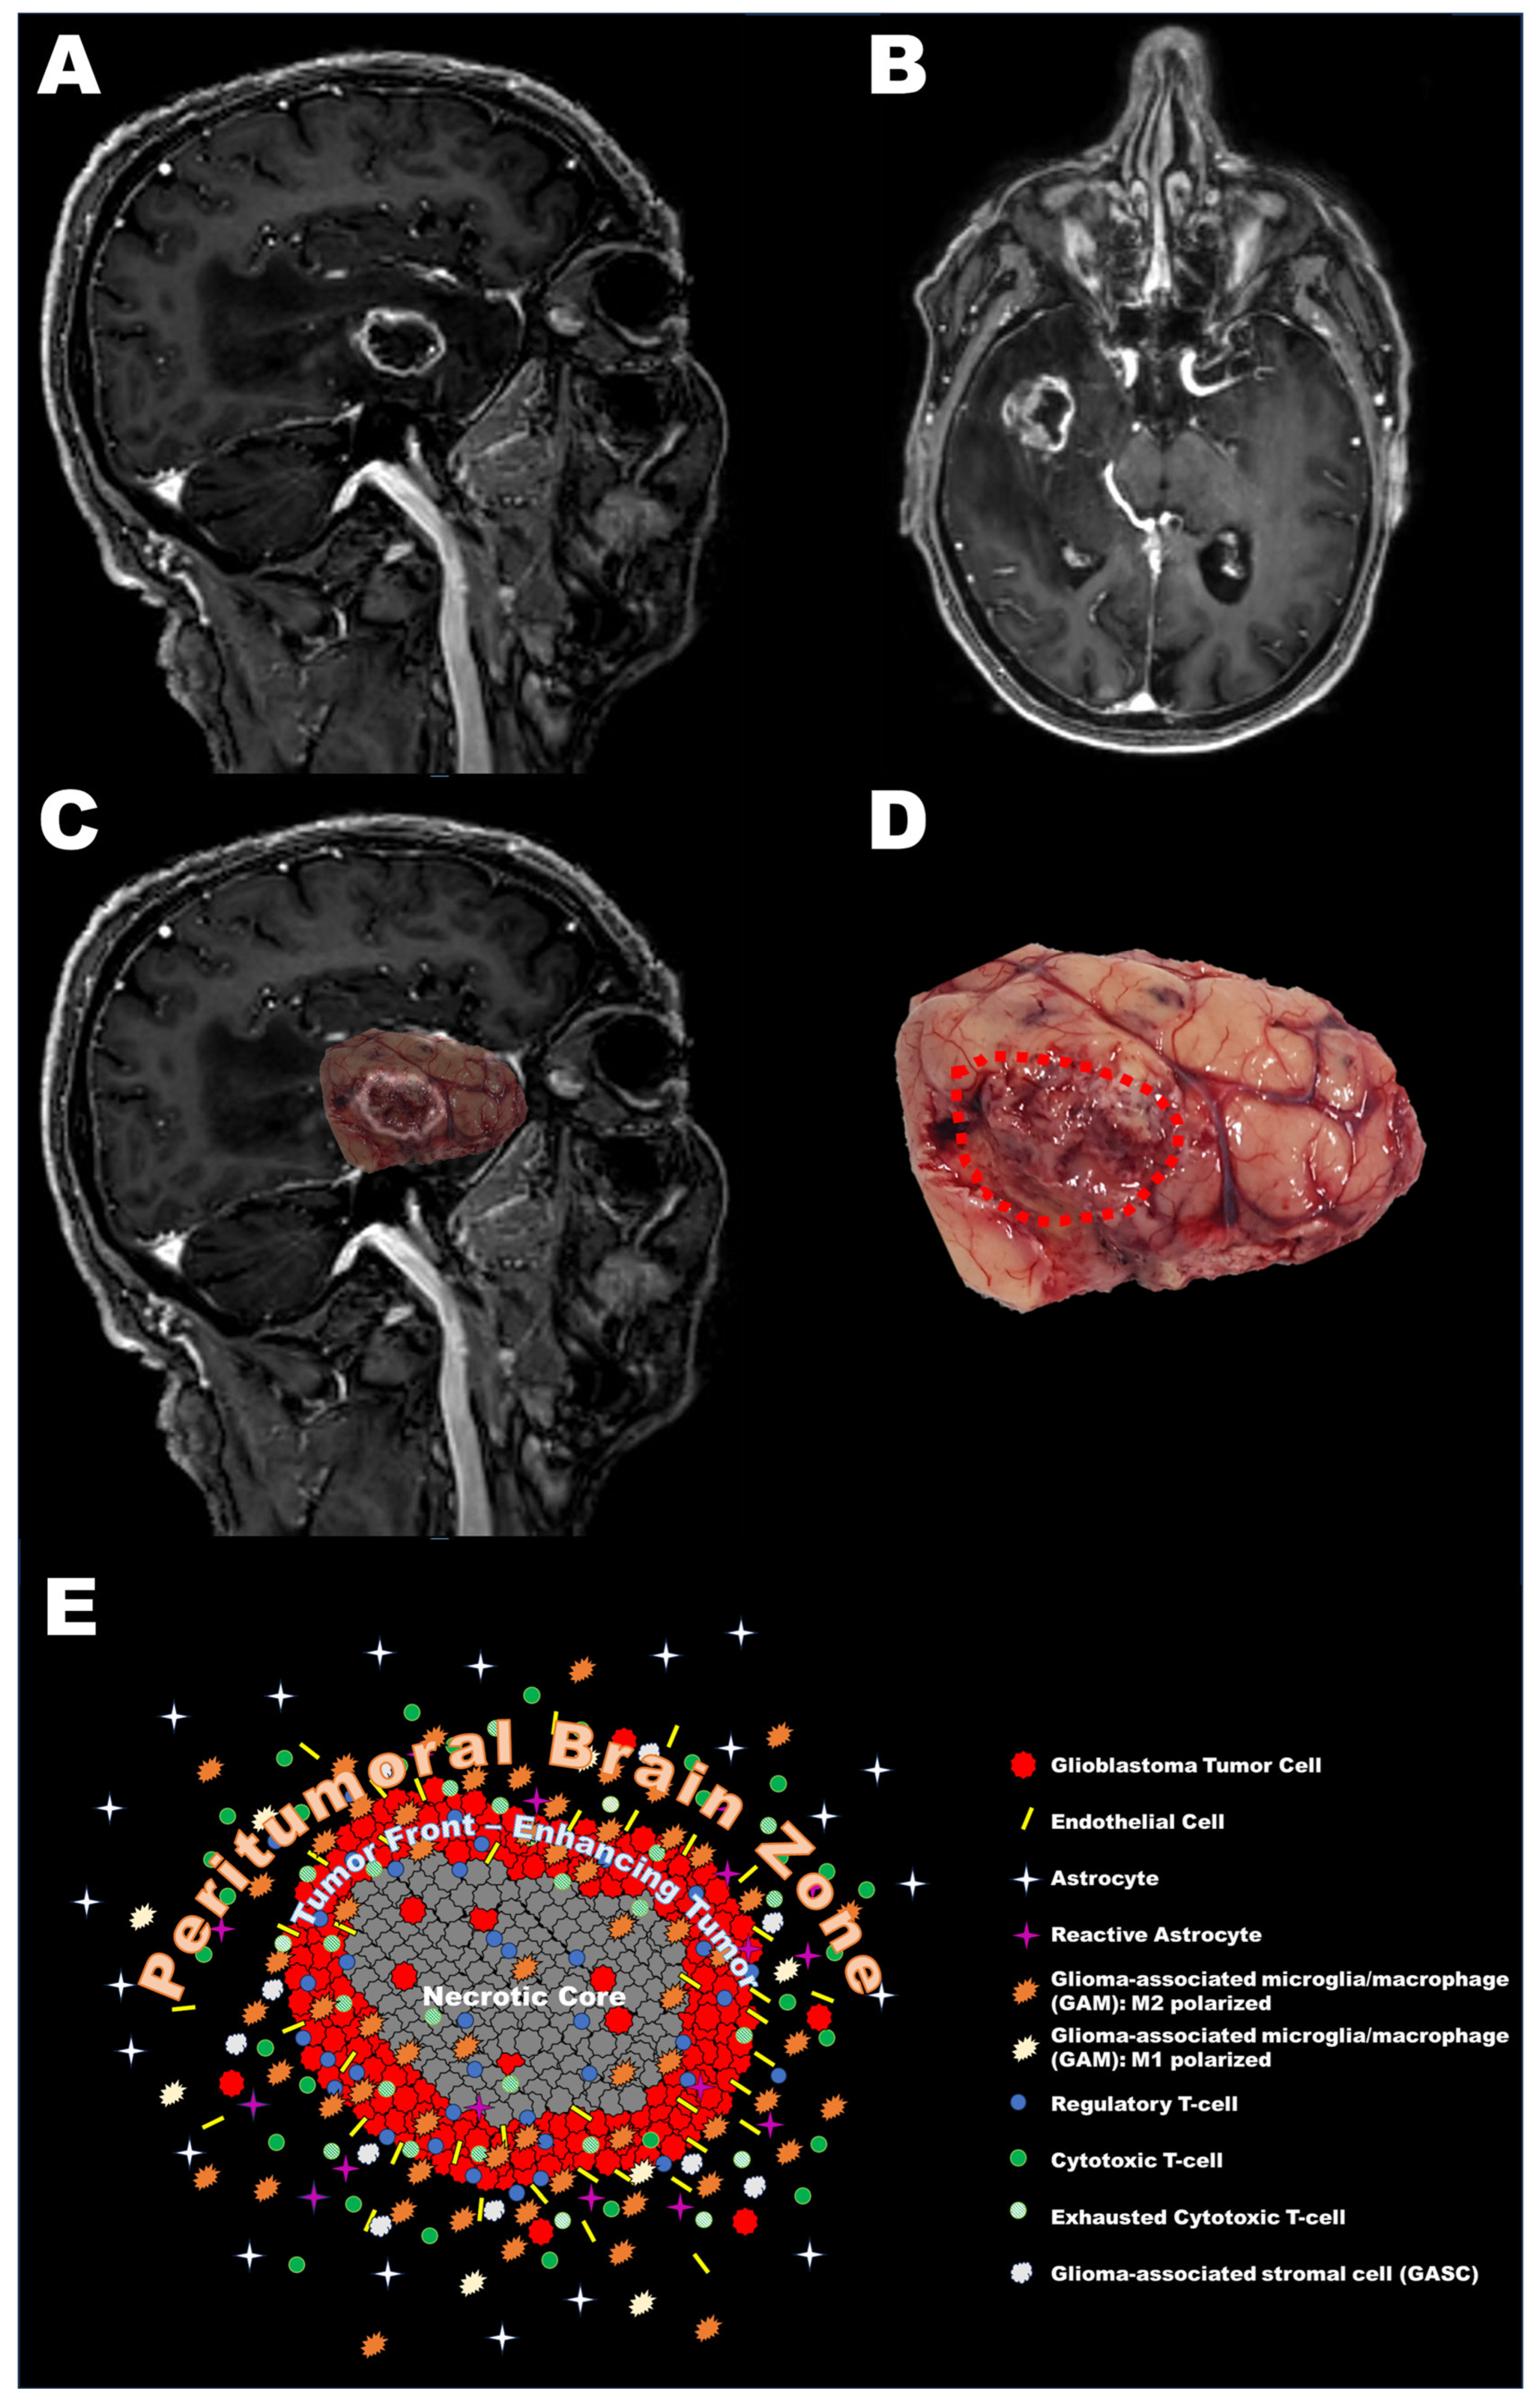

2. Definition of the Peritumoral Brain Zone (PBZ)

3. Cellular Characteristics of the PBZ

3.1. Tumor Cells

3.2. Non-Neoplastic Cells

3.3. Summary of Cellular Characteristics of the PBZ